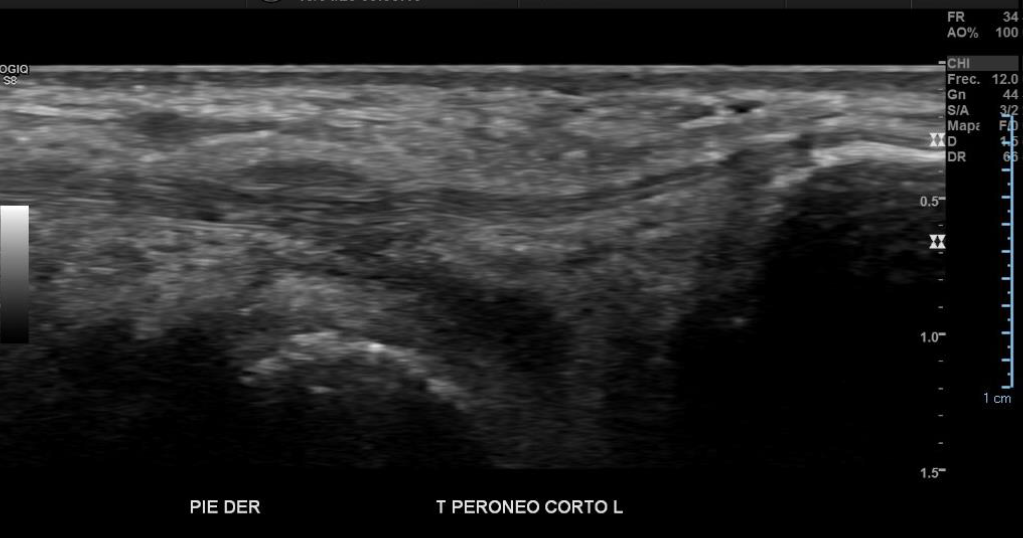

Engrosamiento y disminución de ecogenicidad del tendón peroneo largo en su región distal, sin desgarros.

Tendón peroneo corto, tibial anterior, extensor del hallux y extensor común de los ortejos de grosor y patrón fibrilar conservados.

Imagen con aspecto de os peroneo de contornos corticales irregulares, con cambios inflamatorios de las partes blandas adyacentes, pudiendo estar en relación a fractura a este nivel.

Impresión diagnóstica: Imagen con aspecto de os peroneo de contornos corticales irregulares, con cambios inflamatorios de las partes blandas adyacentes, pudiendo estar en relación a fractura a este nivel. Se sugiere evaluar con radiografía.

Tendinosis del peroneo largo en su región distal.